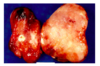

follicular carcinoma

2nd ost common form of thyroid ca

slowly enlarging painless nodule

more common in areas w iodine deficiency

range from encapsulated to widely invasive tumors with necrosis and hemorrhgage

lower survival (age, size, invasion, metastasis)

follicular carcinoma